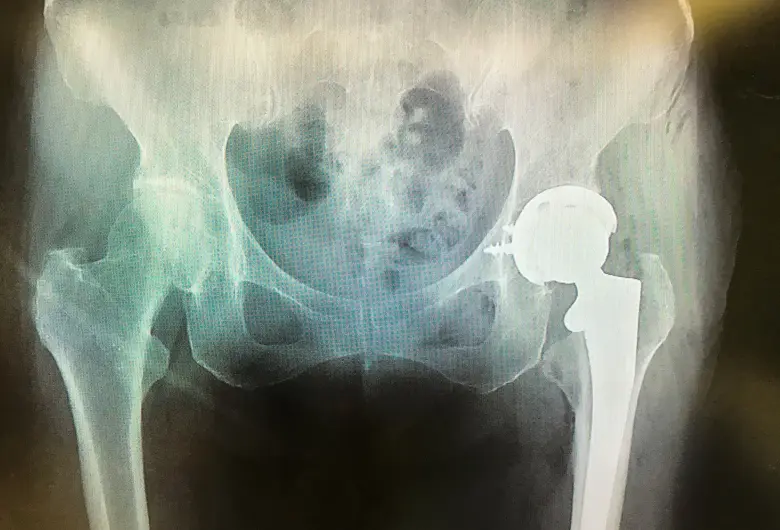

手術前

手術後